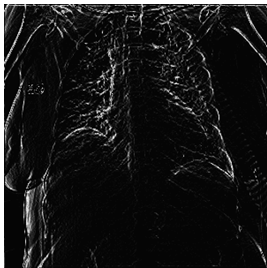

The following findings demonstrate the successful testing of the fuzzy edge detection technique proposed in this study. These results show how fuzzy image processing procedures based on fuzzy edge detection algorithms are carried out, and the resulting images are displayed using MATLAB and an FPGA device.

First: the performance metrices for the proposed edge detection technique is measured for healthy sample images using MATLAB and Zynq702 FPGA. The results of these performances are shown in Table 2 for 299×299 size images.

Table 2 and Table 3 illustrate both the healthy and infected images, respectivly, the clarity of edges is observed. The tables indicate that using the proposed method with MATLAB led to a significant improvement in edge clarity in the Infected images compared to the healthy ones. This is due to the characteristics of the COVID-19 disease present in the infected images, which increase the complexity of the edges and make them less clear. They also indicate that the images produced by the proposed method are clearer than those from MATLAB, as the proposed method employs fixed-point arithmetic to represent numbers that are closer to edge values than the numbers used by MATLAB, which relies on floating-point arithmetic.

Table 2. Results for normal images

Input Image

MATLAB Result

FPGA Result